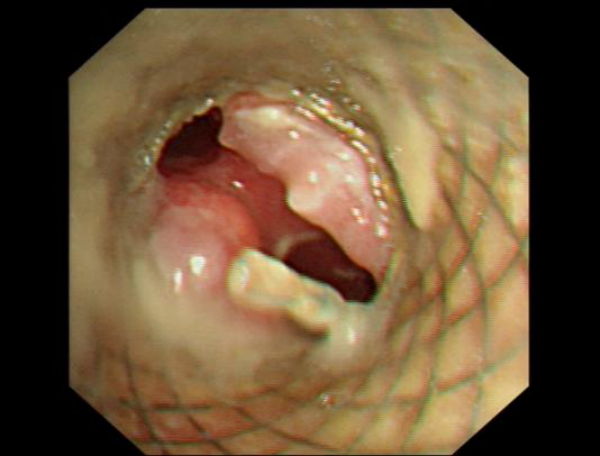

1 术前 (直筒支架远端气道狭窄 )

2 术后(主气道及双侧支气管明显通畅)